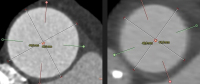

Personalisierte chirurgische Behandlungen bei Erkrankungen der aufsteigenden Aorta // Personalized surgical treatments for diseases of the ascending aorta

Journal für Kardiologie - Austrian Journal of Cardiology 2026; 33 (3-4): 64-69 Volltext (PDF) Summary Abbildungen